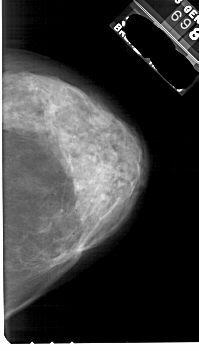

A_1844_1.LEFT_CC

LEFT_CC LINES 5491 PIXELS_PER_LINE 3226 BITS_PER_PIXEL 12 RESOLUTION 43.5 OVERLAY